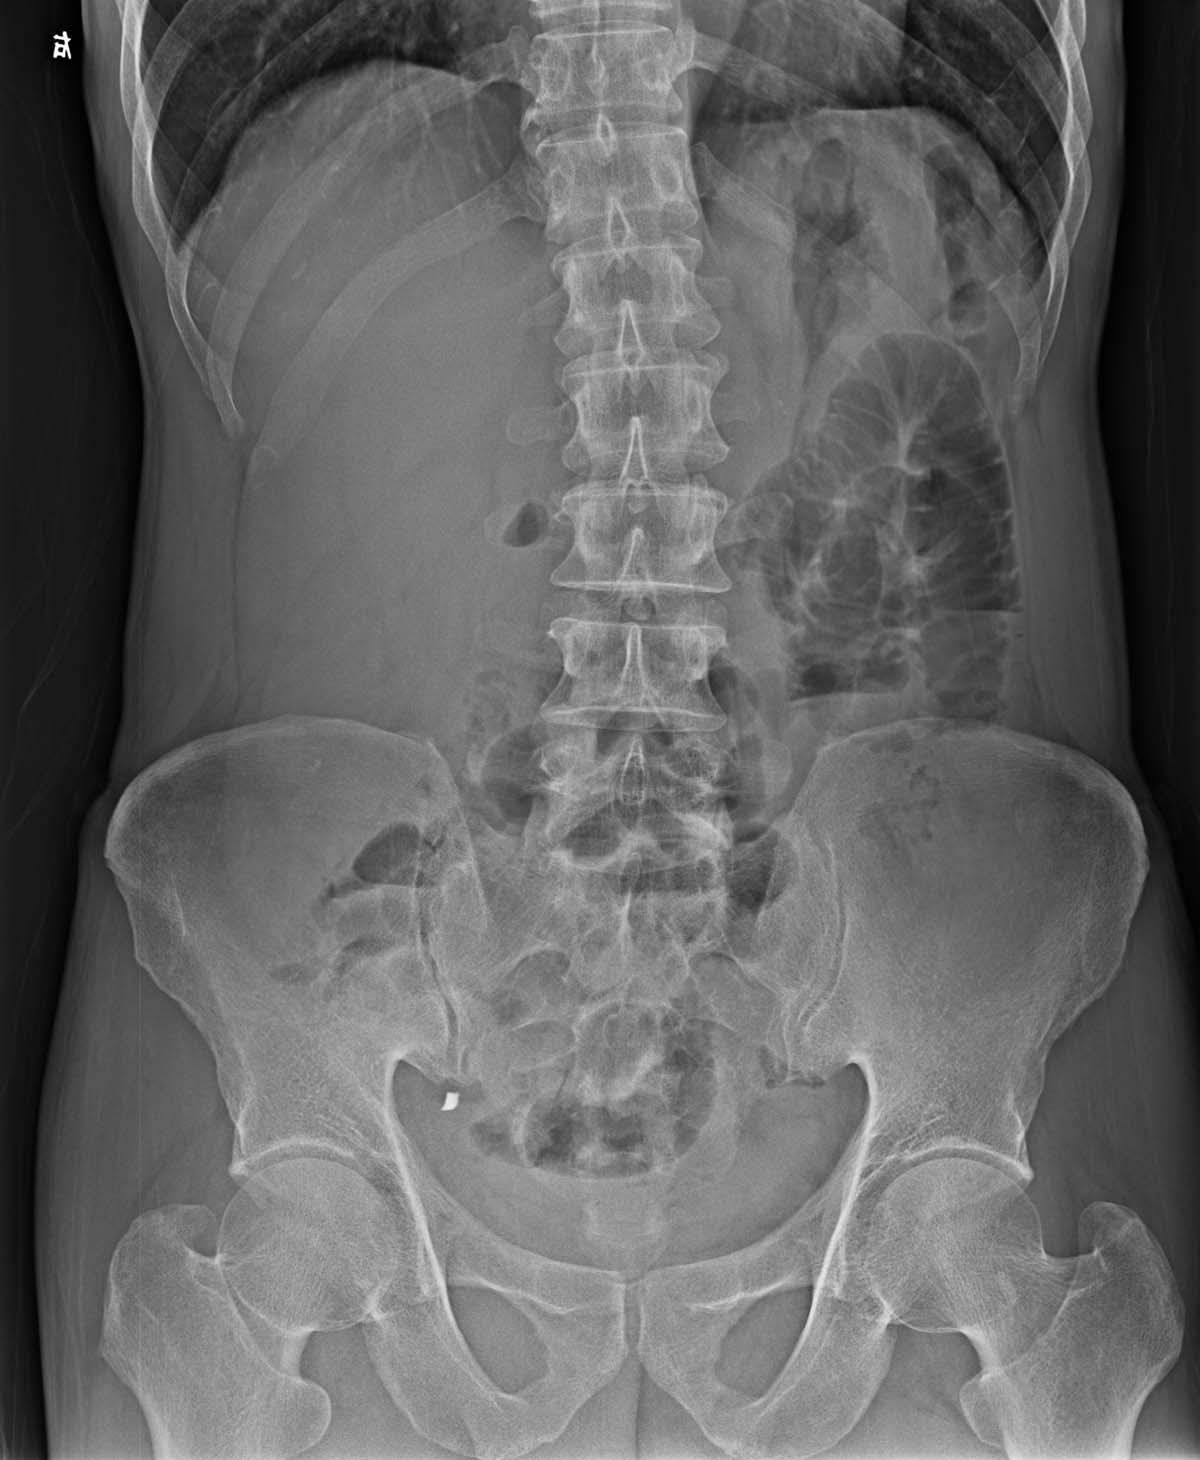

以下是引用xulianj在2007-6-19 22:06:00的发言:[br]ct能解决

以下是引用tfq6909在2007-6-20 14:28:00的发言:[br]不要猜了,ct查一下,病史很重要。